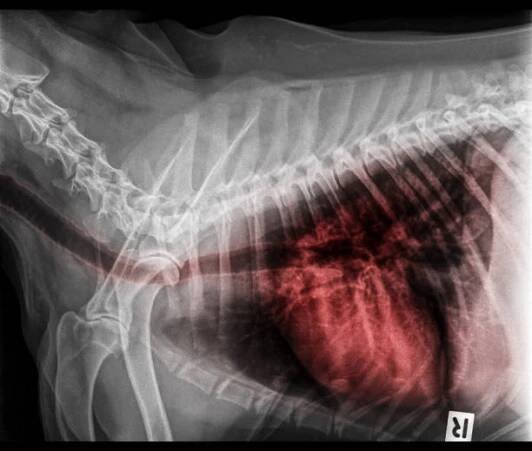

rentgen bočního pohledu psa uzavřený v hrudníku a hrudníku s červeným zvýrazněním v průdušnice dýchacího systému do plic známky pneumonie a bronchitidy- veterinární medicína a veterinární anatomie - pneumotorax - stock snímky, obrázky a fotky